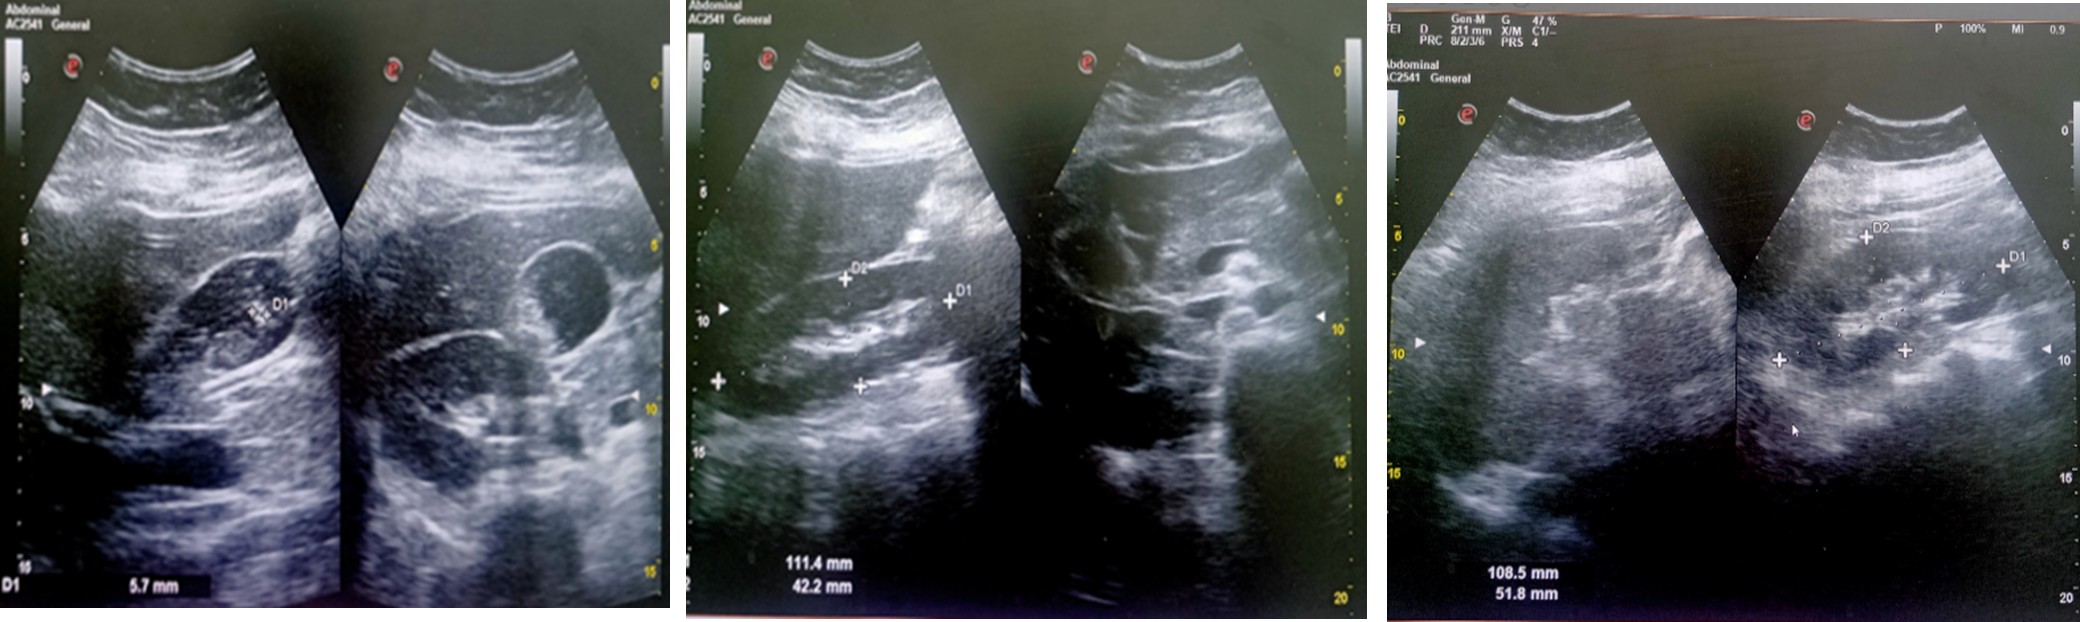

Abdomen scan (18.10.2025)

- Mild hepatomegaly.

- Abdomen scan (04.11.2025) Hepatomegaly with grade 1 fatty change Cholelithiasis and sludge in gall bladder.

Imaging examination (Abdomen scan (04.11.2025)